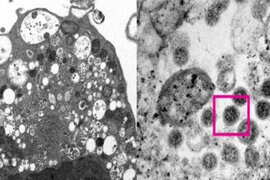

Yaponiyanın Kyoto Tibb Universitetinin tədqiqatçıları Çinin Vuhan şəhərində Kovid-19-un ilk yoluxma halı ilə variantlar arasındakı fərqləri araşdırıblar. -a istinadla bildirir ki, BioRxiv-də paylaşılan tədqiqat nəticələr